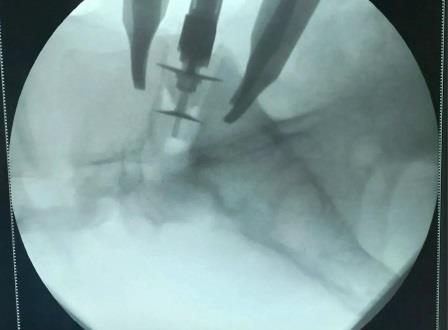

В Волгограде внедряют новую методику лечения грыж межпозвонковых дисков. Такая операция, как артродез позвоночника с передним внебрюшинным доступом (ALIF), сводит риск рецидива практически к нулю.

Хирург получает возможность работать на передней части позвоночника. Он полностью удаляет межпозвонковый диск, а на его место ставит имплантаты, которые правильно фиксируют позвонки и освобождают сдавленные нервные корешки.

От болей в спинах по новой методике уже избавили трёх пациентов регионального нейрохирургического центра, расположенного на территории областной больницы № 1. Два вмешательства прошли на уровне L5-S1 (между поясничным позвонком и крестцом), одно – на уровне L3-L4 (между третьим и четвёртым поясничными позвонками).